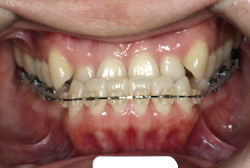

凸凹を主体としたケースの場合、当院の平均治療期間は18ヶ月ですので、このケースは少し長めに経過しました。理由の一つは凸凹の程度がかなり重症だったと言うことですが、もう一つは、右下第2大臼歯が45度くらい前傾していたため、それを整直化させるために時間を要したと考えています。いずれにしても最終結果は大変よい状態と思います。

治療前は並びが乱れて見た目が悪いというのはもちろん問題ですが、歯科医学的に一番困るのは噛み合わせが悪いという点です。上下の犬歯(3番目の歯)は、上下的に離れた位置にあるため接触することができません。つまり歯としては存在していても、歯としては機能していないということです。

凸凹の強弱とは関係なく装置を最初に付けて数日は強い不快感・疼痛がありますが、数日~2週間で慣れてきます。特にこの症例のように凸凹が厳しい場合は、凸凹の歯の表面にさらに凸凹した装置が付きますので、非常に歯が磨きにくくなり虫歯や歯周病のリスクが高まりますので、歯磨き指導を十分に受けて、セルフメンテナンスに努めることが重要です。

本症例のように前歯部の凸凹が強い場合、歯間部歯肉が痩せて退縮する場合があります(ブラックトライアングル)。またマルチブラケット法全般に言えることは、口腔粘膜の違和感、金属アレルギー、歯根吸収などのリスクがありますので、事前に担当医より詳しい説明を受けて下さい。